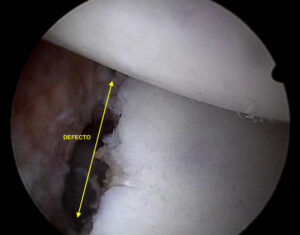

En una entrada anterior del blog hablábamos acerca de la inestabilidad de hombro, sus aspectos generales, y cómo era importante identificar si había un defecto de hueso asociado. En estas

El hombro es la articulación más móvil del cuerpo. Debido a su peculiar anatomía, en la que la superficie articular de la glenoides es mucho más pequeña que la cabeza